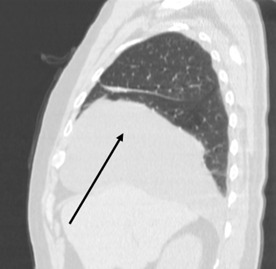

Рисунок 1. Обзорная рентгенограмма грудной клетки пациента Ж., тень кисты перикарда указана стрелкой

Представленный ниже клинический случай показывает пример бессимптомной кисты перикарда, диагностированный случайно, во время прохождения обзорной рентгенографии грудной клетки.

Пациент Ж., 50 лет, госпитализирован в плановом порядке в отделение хирургии КГП «Многопрофильной больницы №1» г. Караганды 29.10.2024 в плановом порядке с предварительным диагнозом «Округлое образование нижней доли правого лёгкого? Киста? Опухоль? Туберкулёз?». Больной не предъявлял каких-либо жалоб. Планировалось оперативное лечение в виде миниторакотомии с диагностической целью.

Наиболее распространенным рентгенологическим проявлением кист перикарда является четко очерченное, одно- или многоочаговое образование круглой или овальной формы с гладкими стенками и диаметром от 1 до 5 см. Однако диагностика кист перикарда может быть особенно сложной и из-за их редкости ещё больше усложняется. Кроме того, когда поражение обширное и затрагивает структуры средостения и грудной клетки, атипичная картина еще больше усложняет диагностику [4].

В нашем случае пациент не предъявлял каких-либо жалоб, ни со стороны дыхательной системы, ни со стороны сердечно-сосудистой системы. Подозрение на кисту возникло при прохождении рутинной обзорной рентгенографии грудной клетки, что послужило отправной точкой в истории его болезни. В дальнейшем использовался золотой стандарт диагностики кист перикарда – компьютерная томография грудной клетки. Однако, даже это не позволило поставить точный диагноз, в связи с чем было произведено оперативное вмешательство с диагностической целью. Выбор пал на миниторакотомию в связи с размерами образования: 19.5х10.5 см по данным КТ. Фактический же размер образования составил 20.0х14.0 см, а объём – один литр. Оперативное вмешательство выполнено без особых технических трудностей, время операции составило – 95 минут. Интраоперационно заключительный диагноз не вызывал сомнений, а гистологическое исследование препарата подтвердило его.